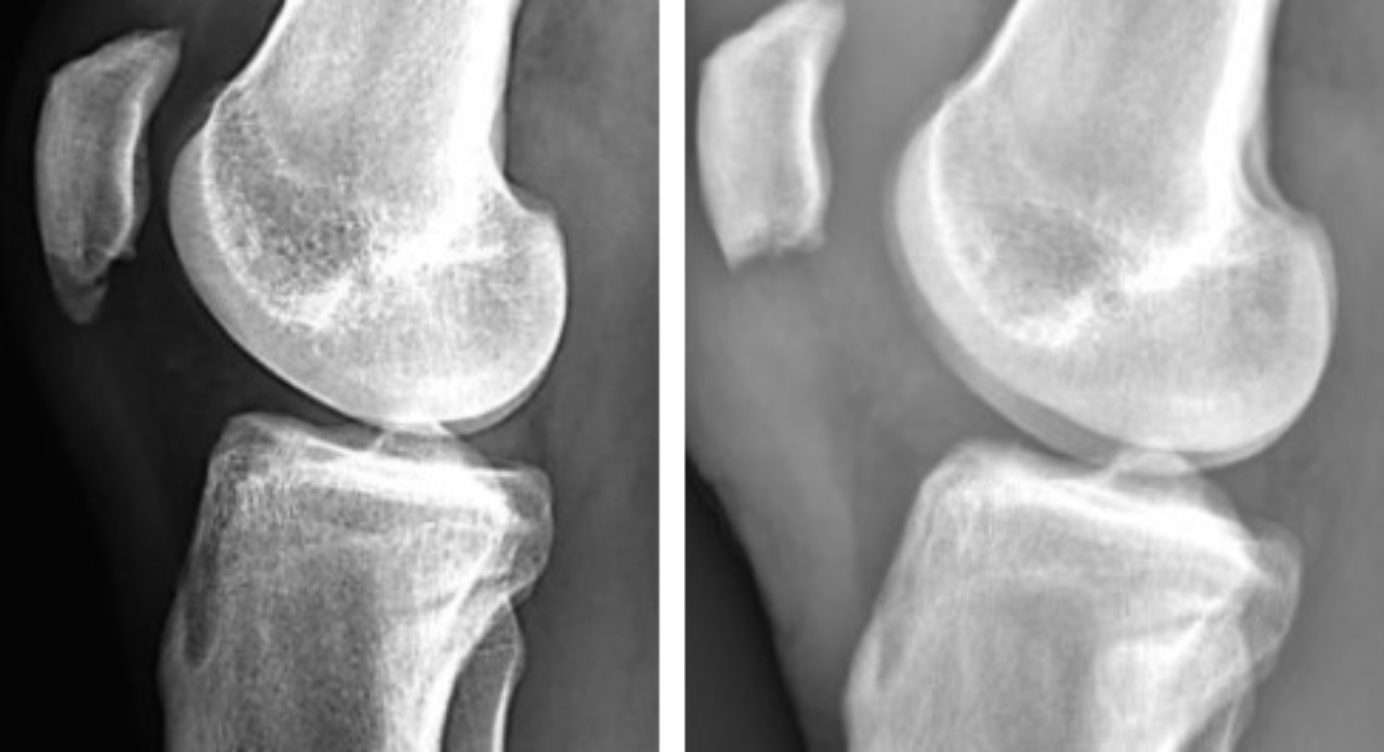

Ларсена йохансона

Ларсена йохансона 146 фото